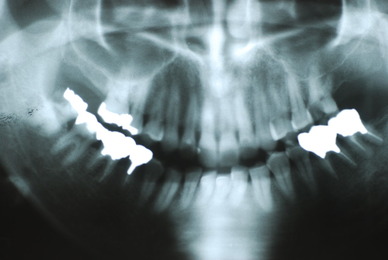

入れ歯の話から入りました。色々不満で注文があるようです。でも話が一段落して口腔内を調べると殆どの歯が重症で抜けそうな歯だらけなのです。

なぜ病気になるのかわからない方が多すぎます。歯が抜けるのは病気だからです。病気を治さずに何かお口の中に入れても土台である歯が抜けてしまっては同じことなのです。

何故歯が悪くなるのか、歯周病で抜けるのか分からなければ何を入れても歯は悪くなり抜けていくのです。